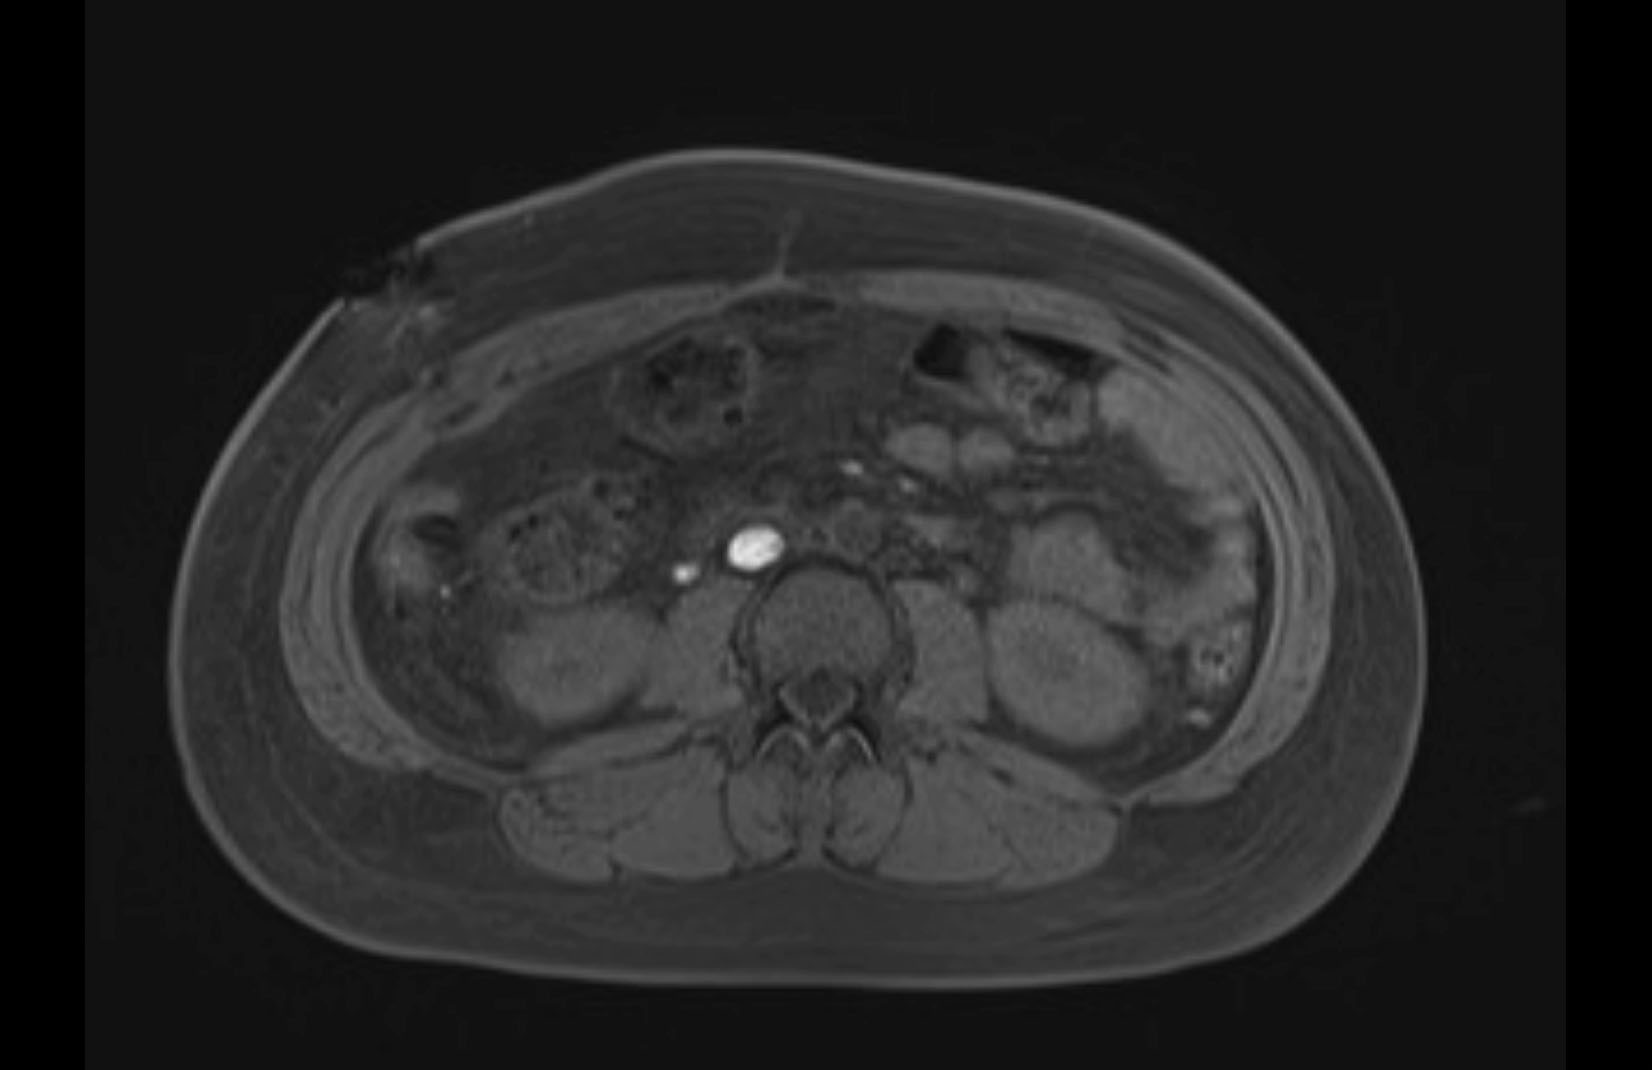

Imaging Analysis

Look through the patient's CT scan to identify any areas of concern for the necessary procedure.

MRI T1

Based on initial findings, which issue(s) would you be most concerned about?